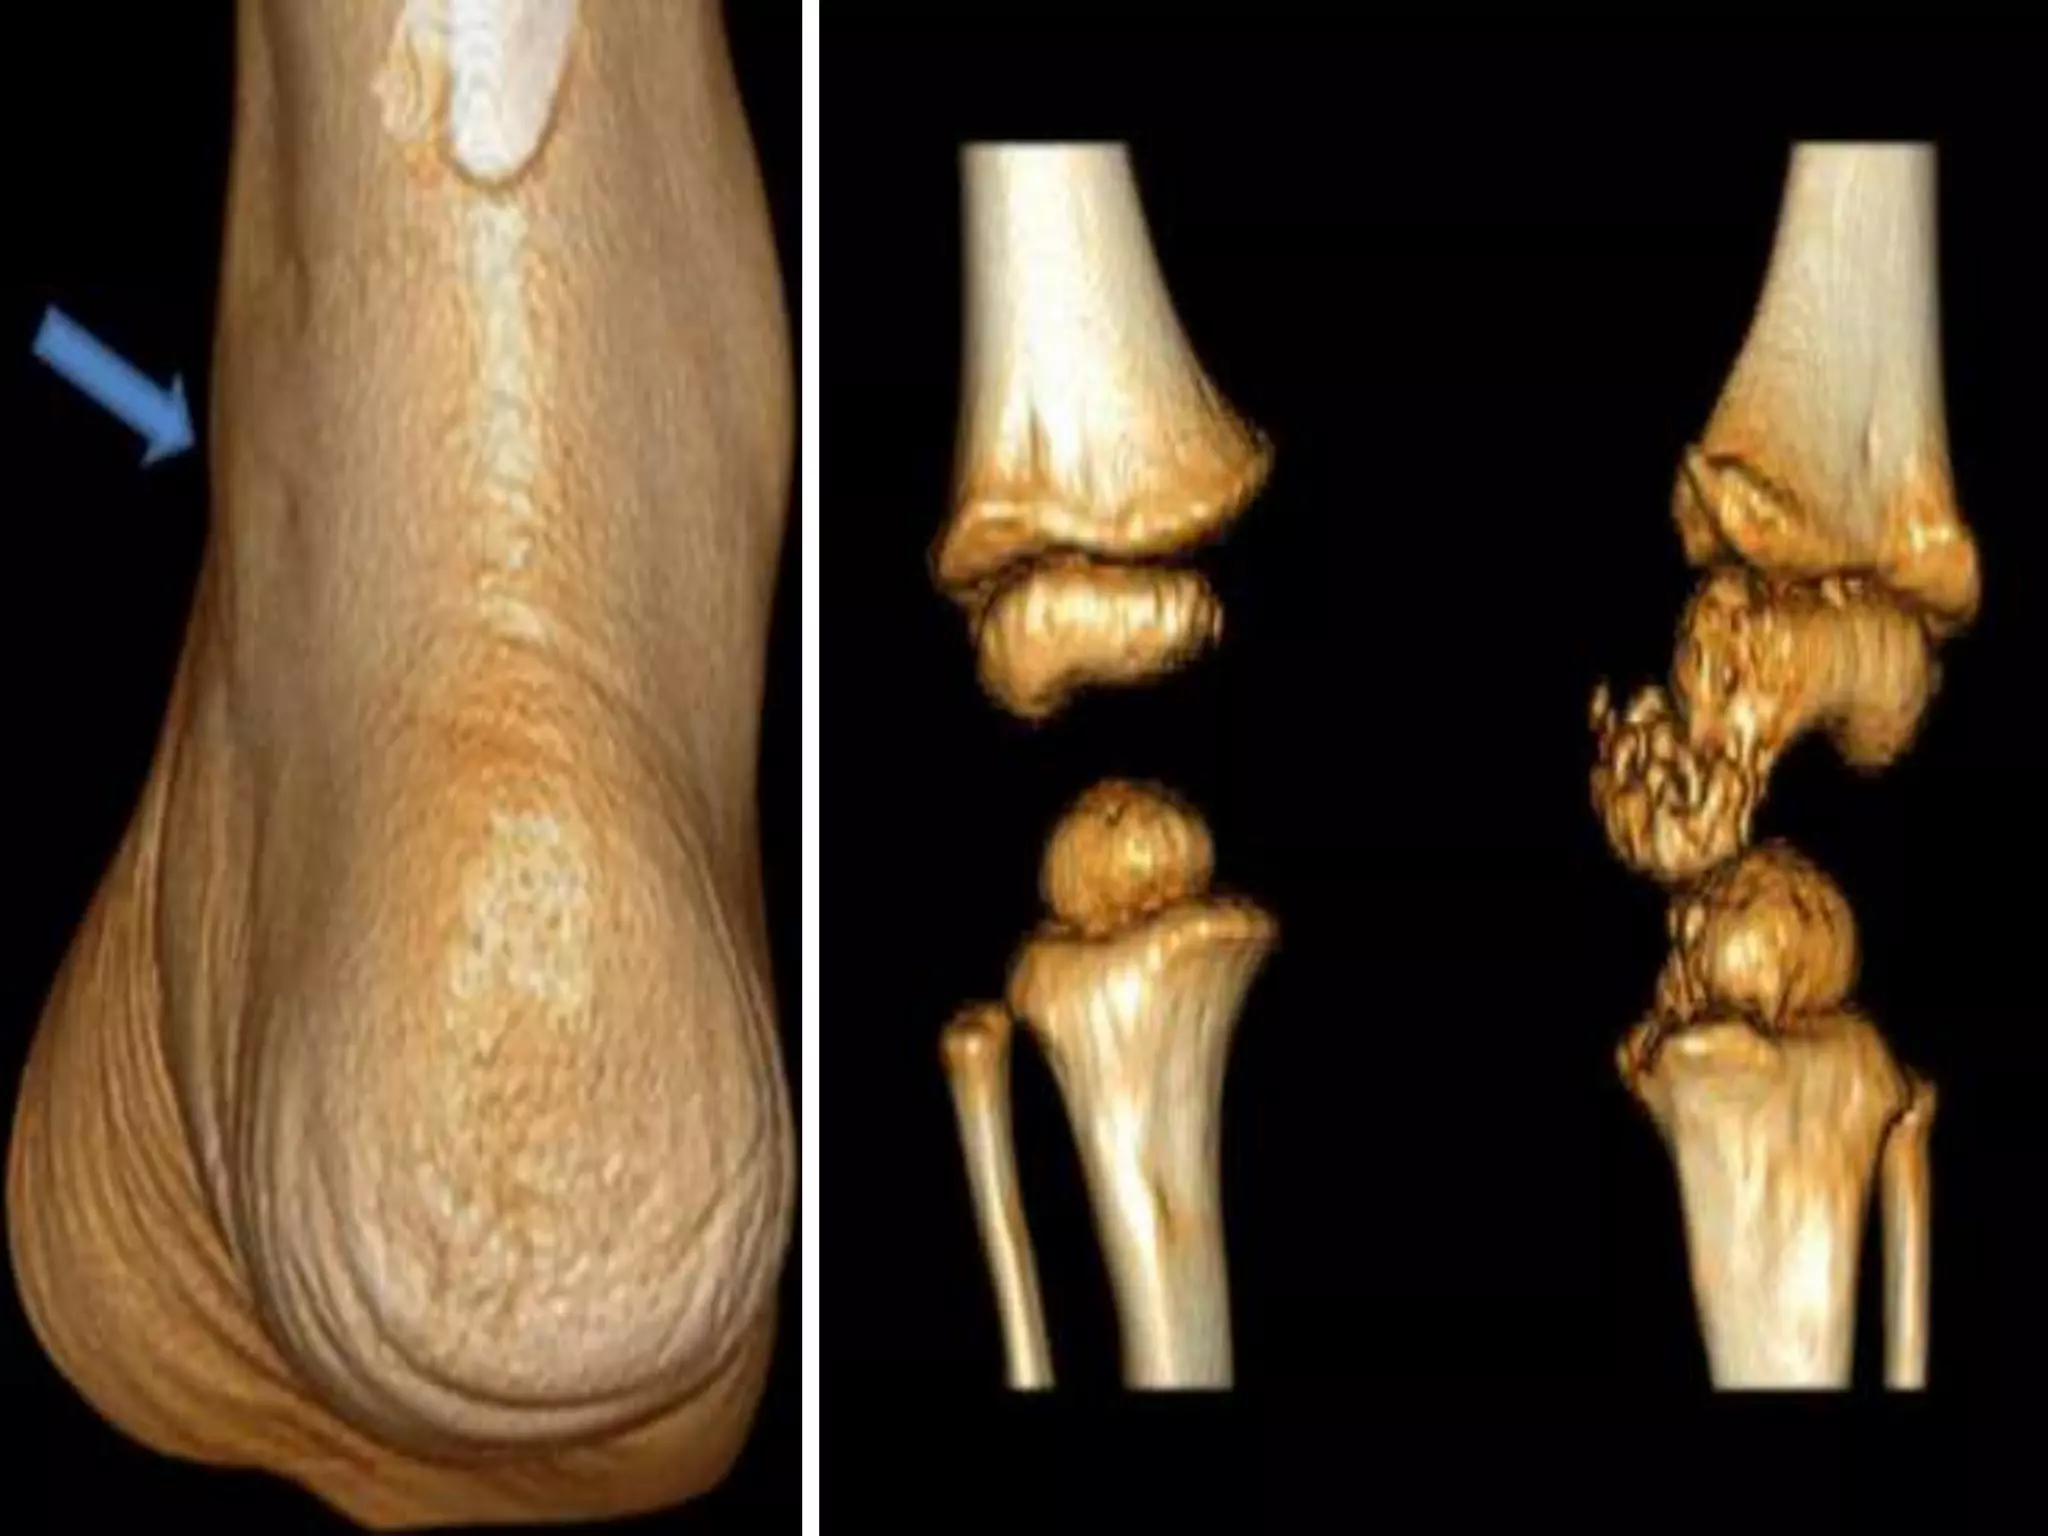

FIBRODYSPLASIA OSSIFICANS PROGRESSIVA

(MYOSITIS OSSIFICANS PROGRESSIVA)

Characterised by ossificans of muscle connective

tissue (trunk mostly)

Starts with fever & inflammation in early childhood

Associated : shortening of big toe & thumb

FIBRODYSPLASIA OSSIFICANS PROGRESSIVA (MYOSITISOSSIFICANS PROGRESSIVA) Characterised by ossificans of muscle connective tissue (trunk mostly) Starts with fever & inflammation in early childhood Associated : shortening of big toe & thumb